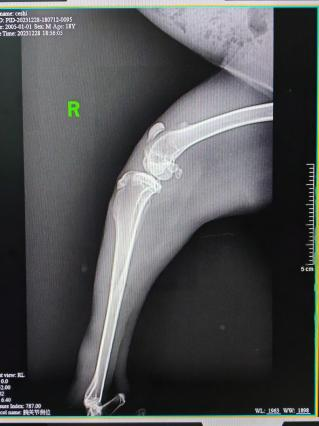

影像学检查

影像学检查:X光、CT、核磁